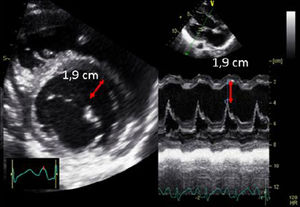

| A.2. Fracción de acortamiento (FA) | ||

| Se trata de un parámetro subrogado de la FE (Teichholz) en la que se valora los DtTDVI y DtTSVI. Presenta las mismas limitaciones que las comentadas en la estimación de la FEVI por Teichholz. | ||

| A.3. Diámetro telesistólico del ventrículo izquierdo (DtSVI) | ||